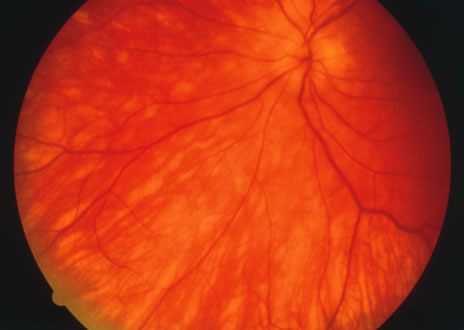

Acutely, there may be creamy white lesions in the posterior pole. These lesions tend to be deep and poorly demarcated. Sometimes these lesions may become confluent. The lesions clear by losing their yellow-white opacification and clearance occurs from centrally to the periphery. With time the lesions resolve leaving mottling of the retinal pigment epithelium (Figs. 5, 6, and 7).

Fig. 5. Fundus photograph showing the acute creamy lesions of a recent case of acute multifocal posterior placoid pigment epitheliopathy.

Fig. 6. Fundus photograph of the same case as in Figure 5. The findings at 1 month after the initial presentation now shows mild pigment clumping and mild retinal pigmentary atrophy.

Fig. 7. Fundus photograph of the same case as in Figure 5. The findings at 7 months following initial presentation show more pigment clumping and retinal pigment atrophy in small circular lesions.